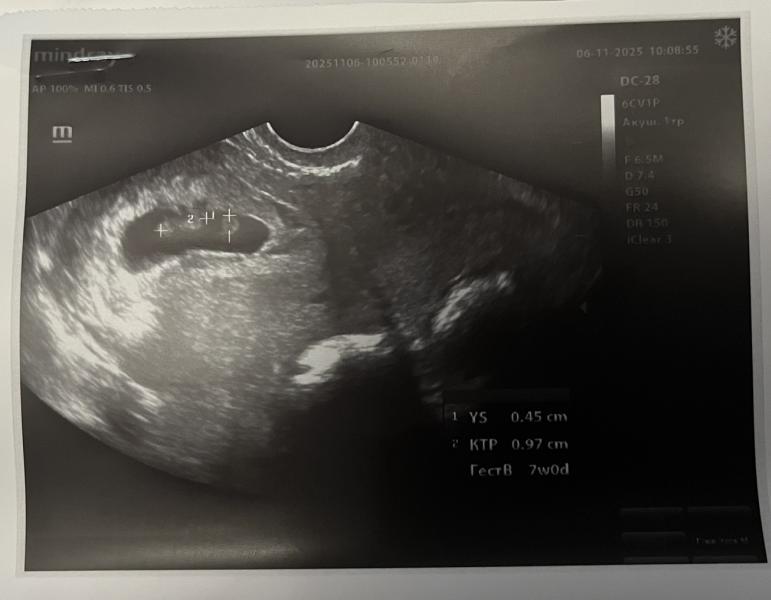

Мне показалось сначала, что там двое 😅. Поздравляю! Отличная новость